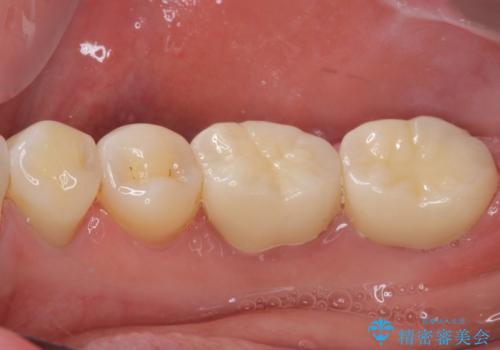

咬合力が強く、土台の歯の高さが低かったたため、より高強度のフルジルコニアクラウンにて補綴治療を行いました。